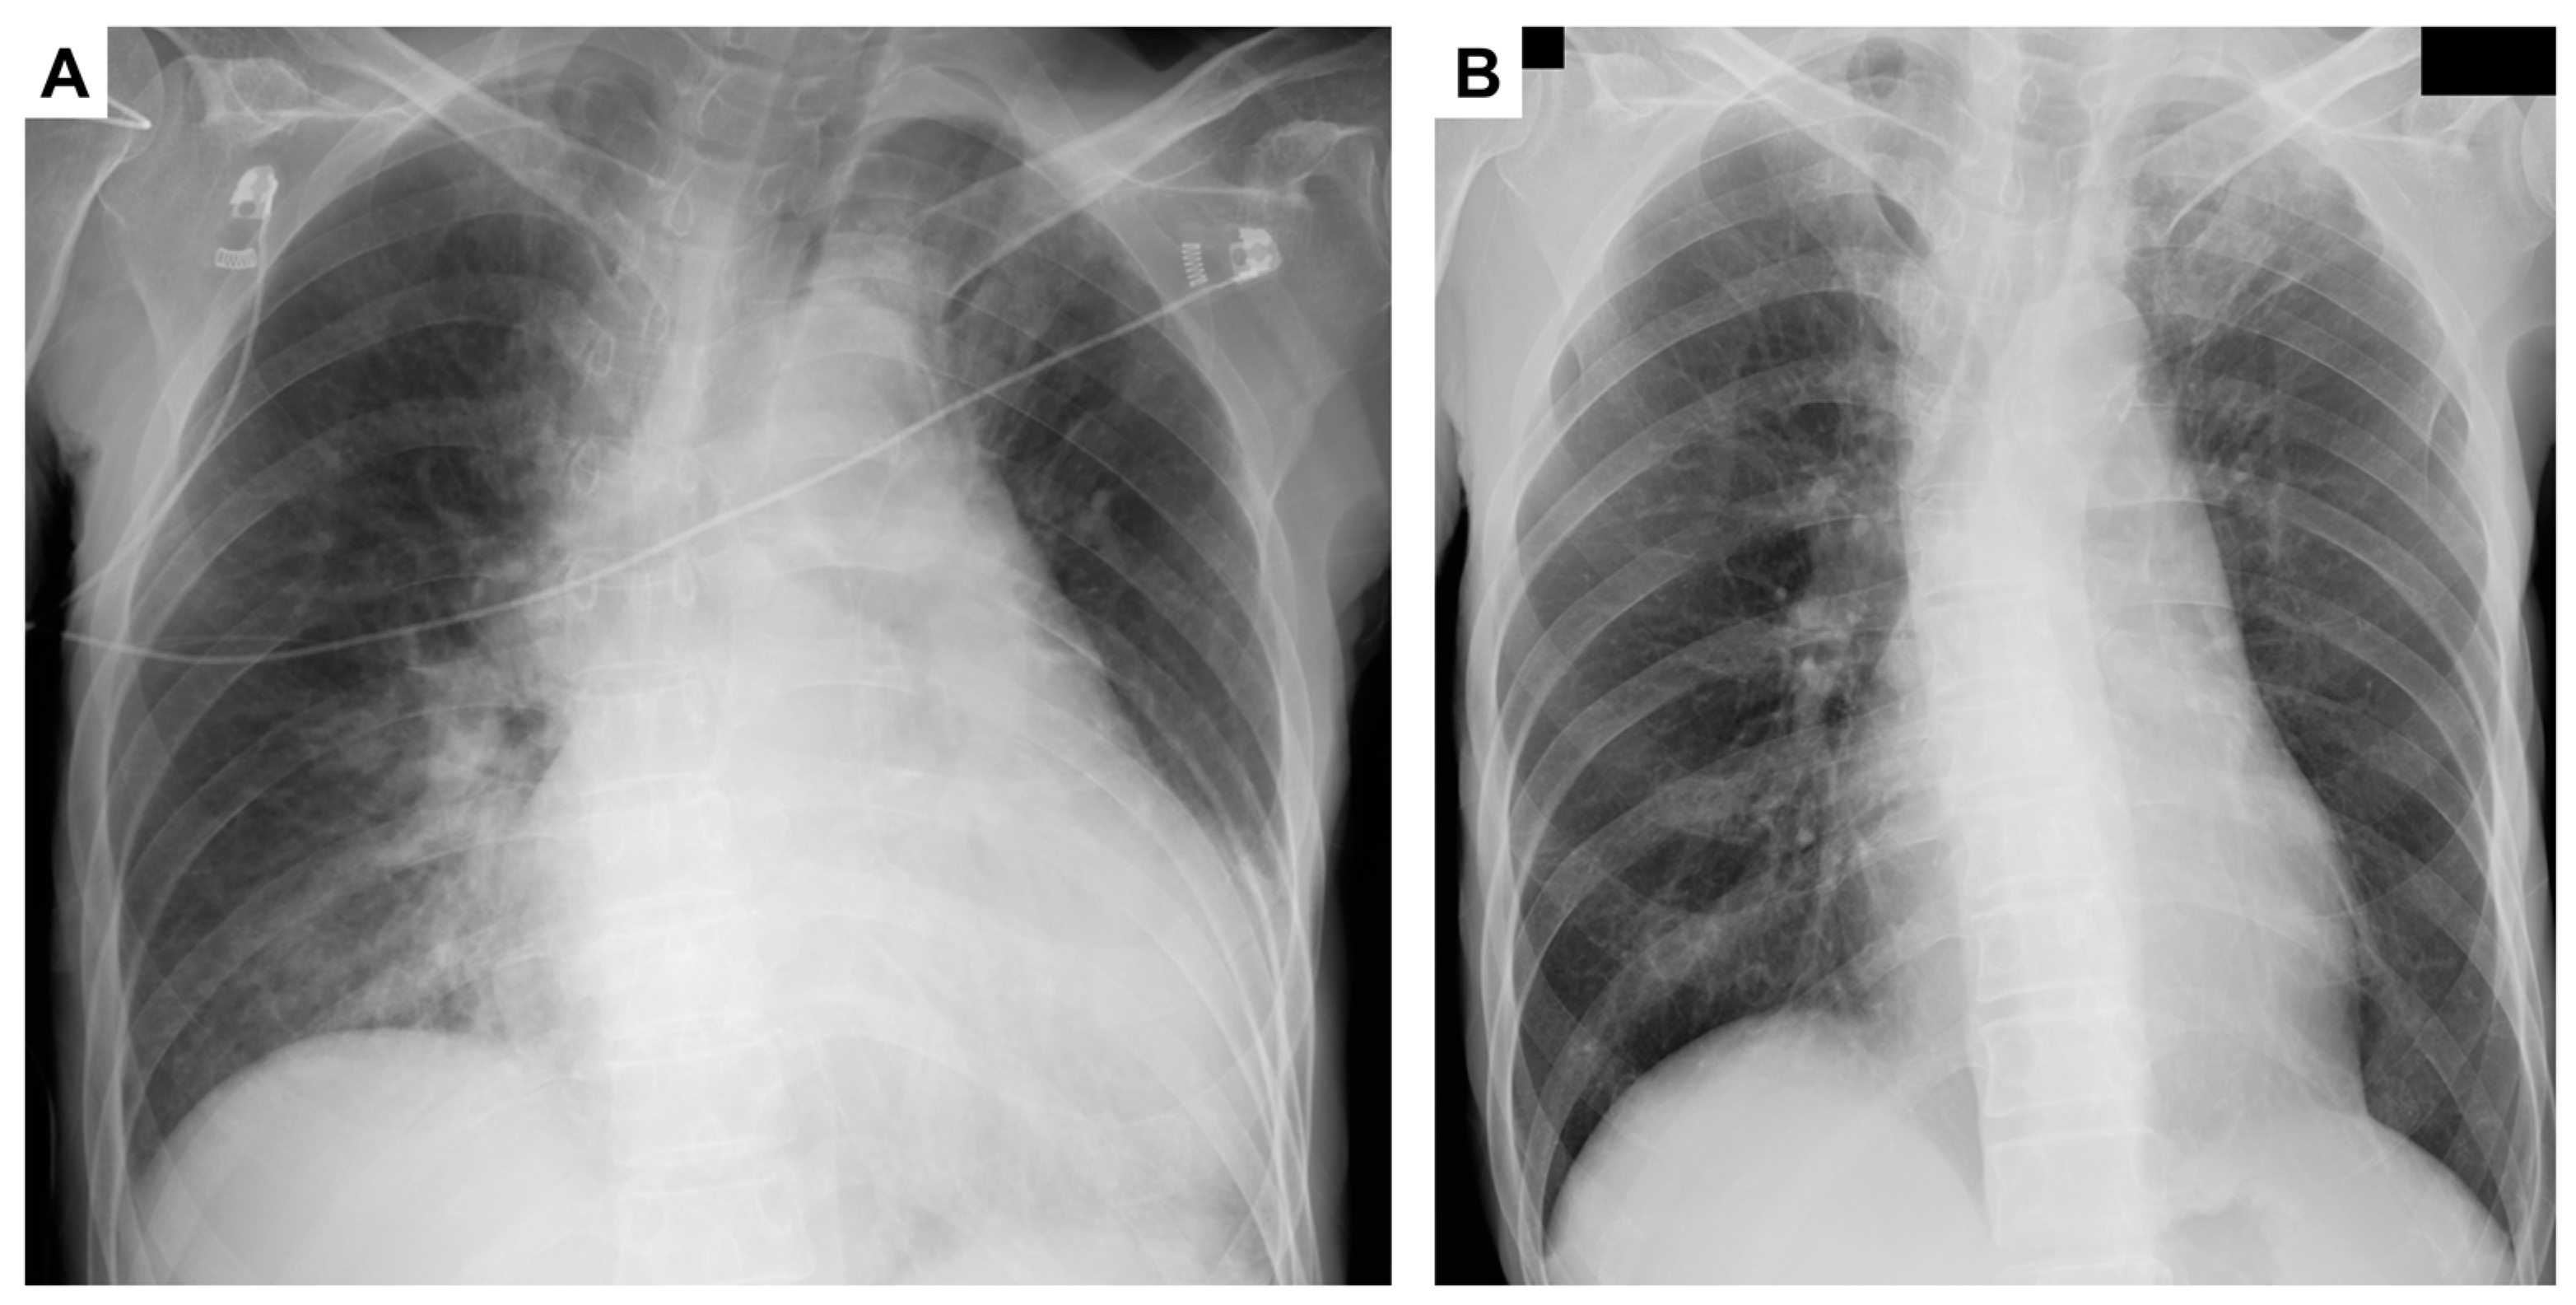

2. Case Presentation